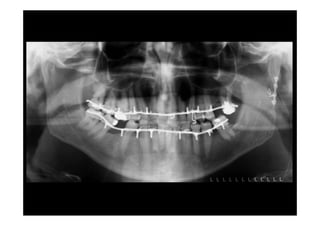

Radiologia:

•    Mandíbula oblícua

•    OPG

•    Oclusal inferieur

•    Retro-alveolaires

Oclusal                         Ralv.

orthopantomographie

Dautrey, Bonneau

mordu, rétro